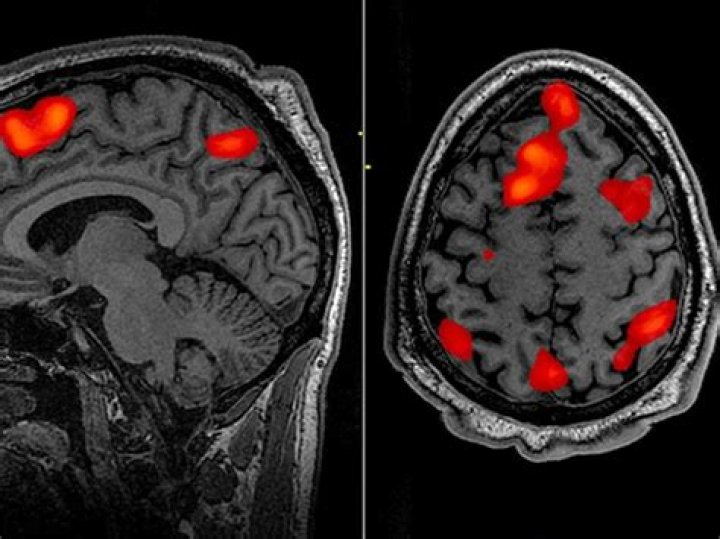

It may be used to examine the brain’s functional anatomy, (determine which parts of the brain are handling critical functions), evaluate the effects of stroke or other disease, or to guide brain treatment. fMRI may detect abnormalities within the brain that cannot be found with other imaging techniques.

fMRI detects brain activity by measuring the changes in both the amount of oxygen in the blood and the amount of blood flow [4, 5]. This measurement is known as blood-oxygen-level-dependent activity (BOLD activity).

fMRI tracks changes in blood flow and oxygen levels to indicate neural activity. When a particular brain area is more active, it consumes more oxygen, and blood flow increases. As the technology was refined, fMRI researchers became able to characterize brain function at the level of neural processes.